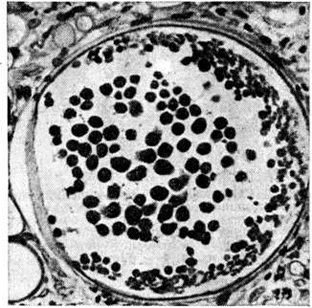

В поражённых тканях на фоне хронический воспаления, наряду с плазматическими клетками, эозинофилами, лимфоцитами и иногда гигантскими клетками типа Лангханса, видны спорангии — толстостенные округлые образования диаметром до 350 микрометров, наполненные эндоспорами (рисунок), а также отдельные споры (диаметром 7—9 микрометров). Возможны микроабсцессы с некрозами в очагах.

Рис

Микропрепарат полипозного разрастания на слизистой оболочке носа при риноспоридиозе: в центре спорангий грибка с эндоспорами; окраска гематоксилинэозином, ×400.